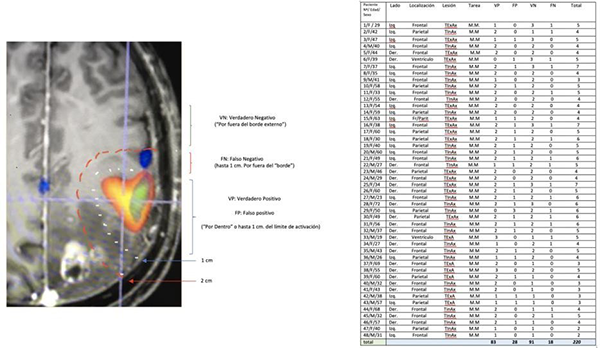

Las respuestas de las áreas de cada sticker se distribuyeron en una tabla estadística de 2 x 2, metodología que nos permitió el análisis de los resultados quirúrgicos.

Se utilizó un test binario (tabla 2 x 2) para validar la respuesta motora en el área de activación de la RMfm. El test de referencia para validar la prueba fue la electroestimulación cortical directa (ECD).

Las respuestas a la ECD (Estimulación Cortical Directa) se clasificaron en este trabajo como: 1 (VP): verdadero positivo: cuando se observa respuesta motora por ECD dentro del área de activación de la RMfm, o hasta un máximo de 1 cm por afuera del “borde”, 2 (VN): verdadero negativo cuando hubo ausencia de respuesta por fuera del “borde” del área de activación de la RMfm, (3)FP: falso positivo ausencia de respuesta motora por ECD dentro del área de activación de la RMfm (ó su borde), 4: falso negativo la presencia de respuesta motora por ECD 1 cm por fuera del “borde del área de activación BOLD.

Resultados de la prueba (Tabla Nº1)

Se realizaron un total de 220 (tabla Nº2) registros luego las respuestas se distribuyeron para su análisis estadístico en una tabla 2 x 2 (tabla N° 3):